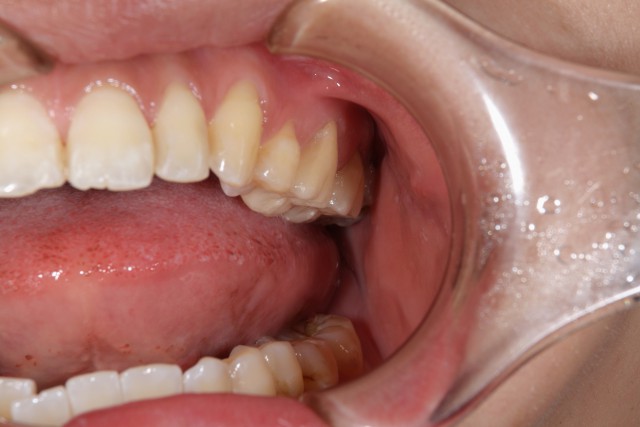

施術中

金属で治療してあったものをはずし土台を形成しなおします。このように自分の歯を土台として使える場合にはそのまま型を取りかぶせるクラウンという施術方法で治療していきます。また、今回のようなメタルフリーの場合黒ずみなどもなくキレイに仕上げることが出来るのもメタルフリーの特徴の一つです。